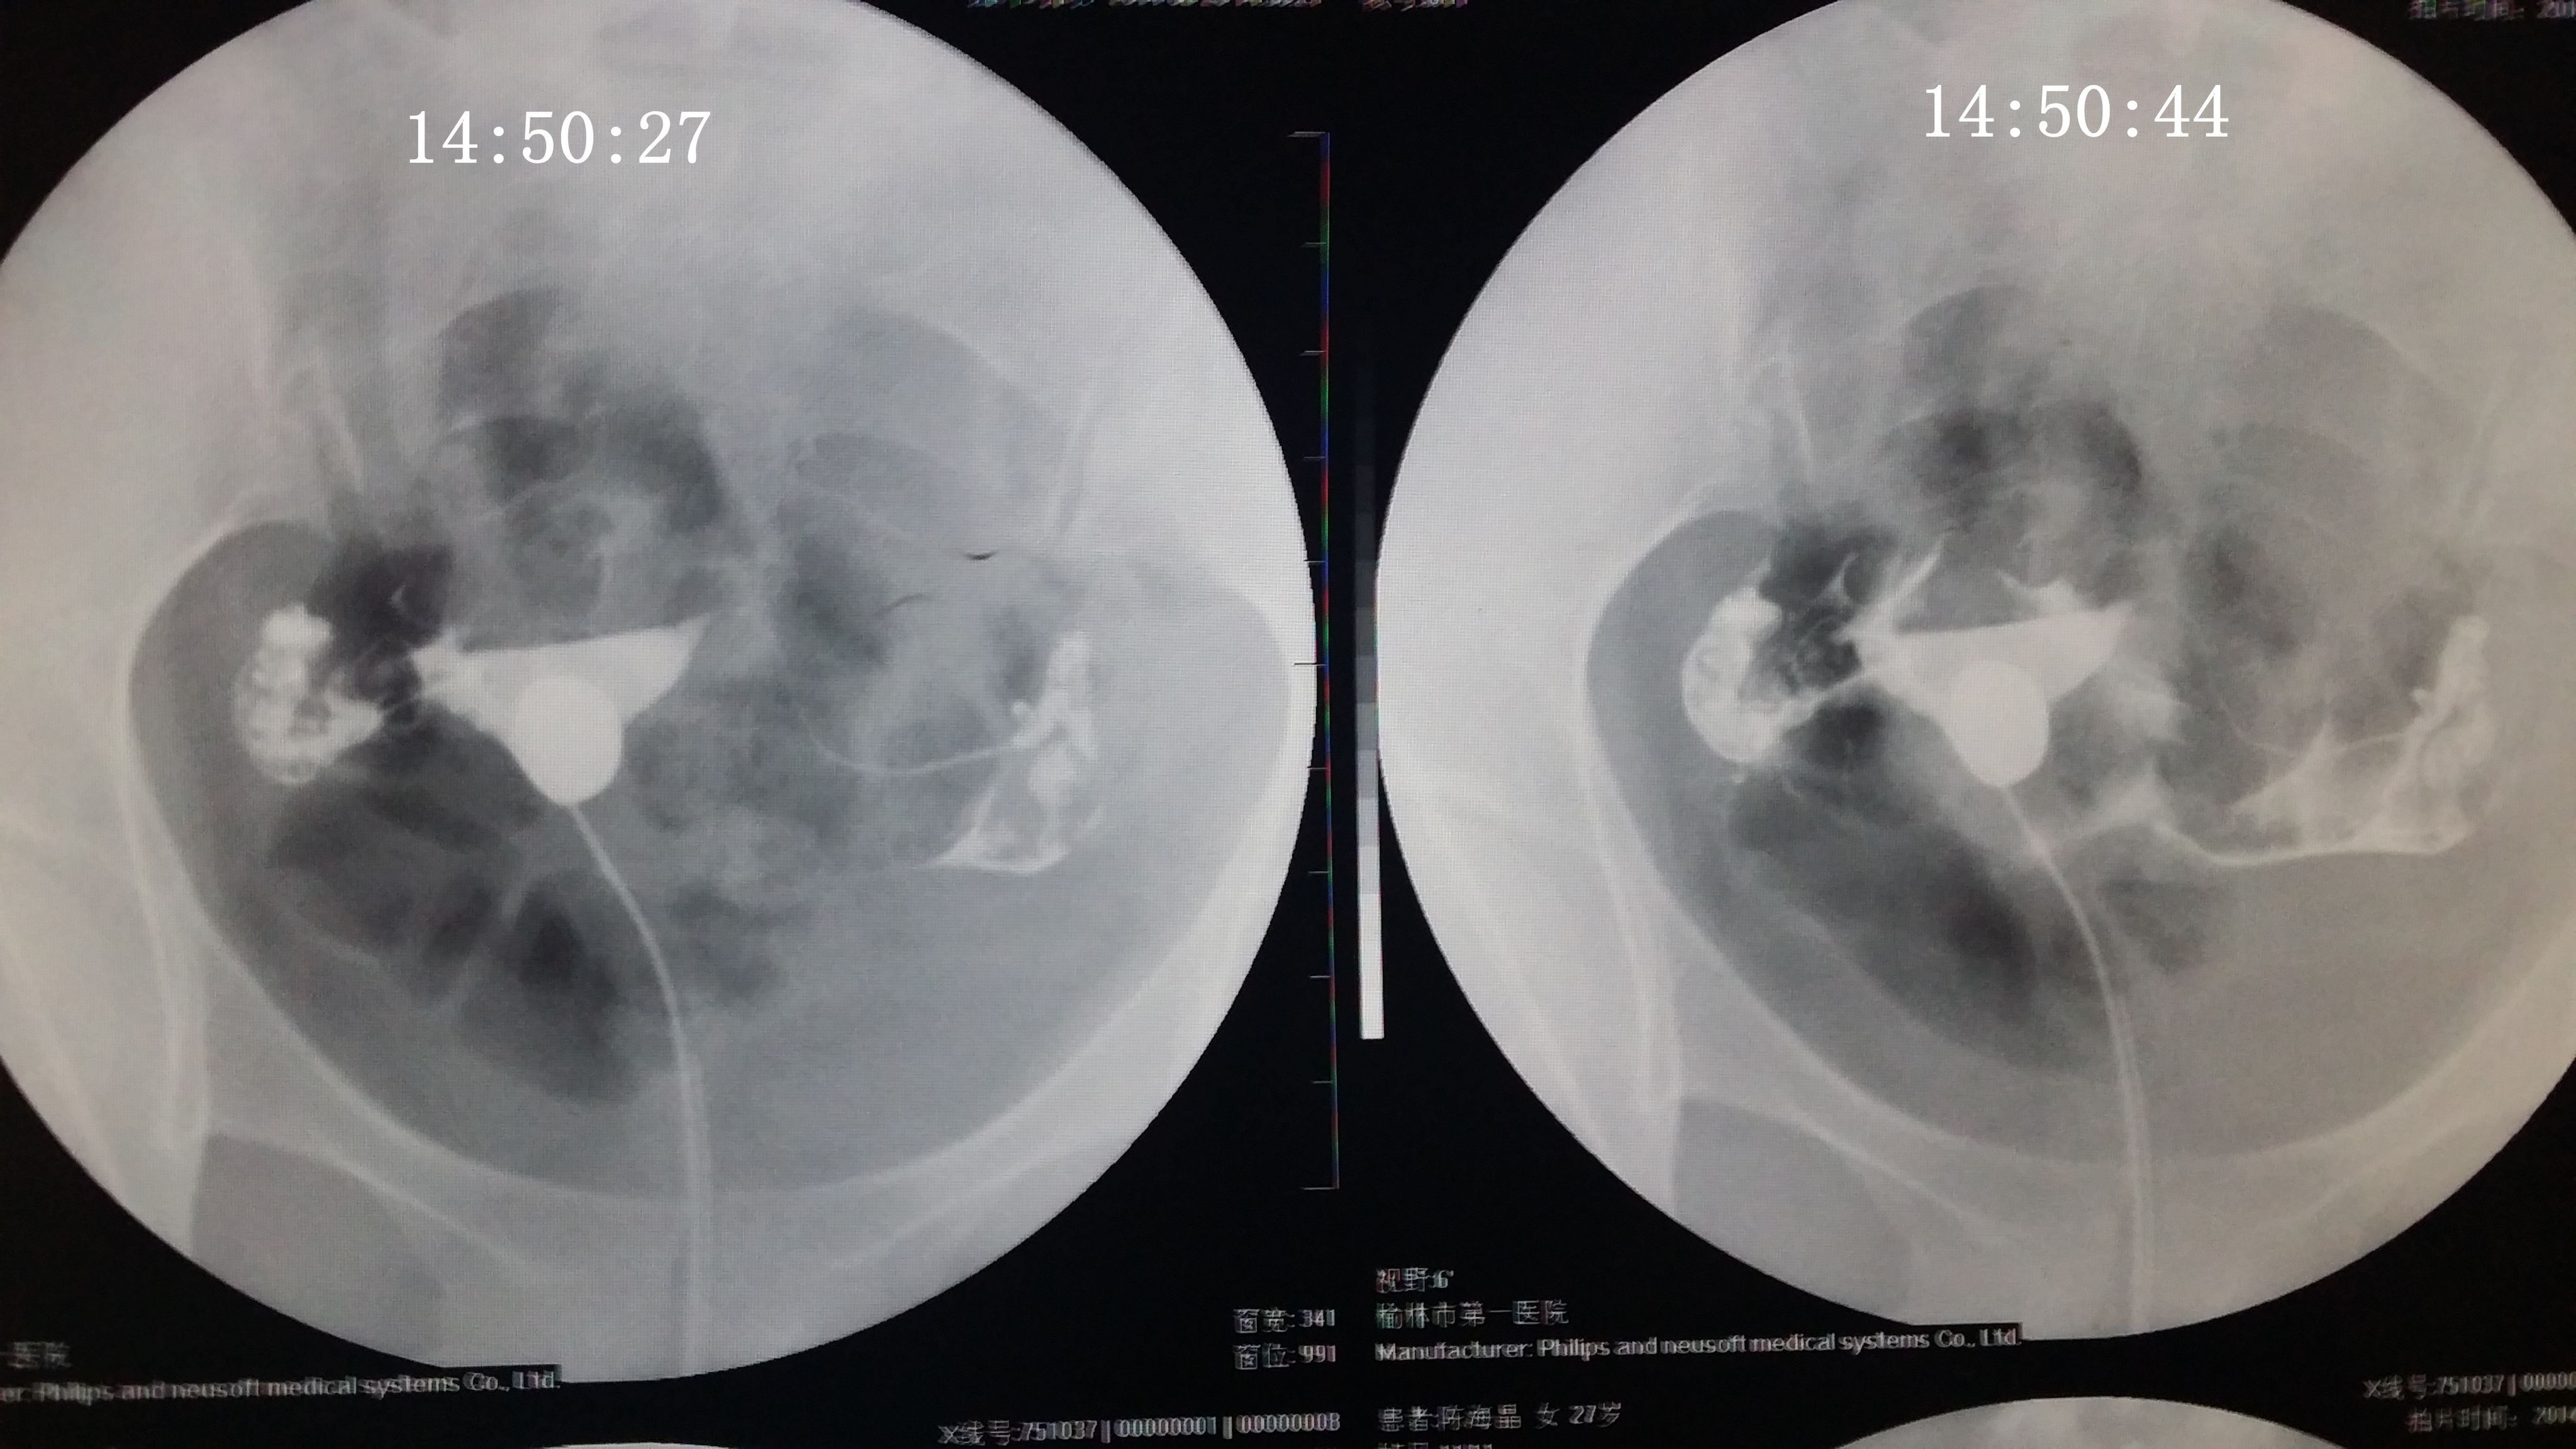

请专家帮我分析下我的造影片 医生诊断说是没问题,只是右侧输卵管伞部有点弯曲不直,说左侧通着可以自 然受孕,不知道会不会有错,之前在其他医院没做造影直接做的通液,说是阻力很大,堵的厉害,后过几个月在另一家医院做的这个造影片。(另之前有过盆腔积液,但已经治疗好了} 造影都好几天了右侧一直觉得酸痛的,是不是又发炎了啊,吃药可以吗? 点击展开 匿名用户 2014-09-04 20:08 为您推荐: 其他回答 你好,现在这个时候你不要太担心的竟然是已经检查过了之后的话那就不要剪的啦,因为这个时候已经通开了, 可靠的悠闲80 2014-09-05 12:50 相关问题 输卵管通而不畅,迂曲右侧上举,请问济南哪个大医院治疗这个专业啊~请有经验的人告诉下~急急急另附造影片 输卵管伞端不通怎么办 如果排了,B超能检测出来吗?B超单上会显示什么?12月22号做的造影,结果是右侧输卵管伞端通而不

然受孕,不知道会不会有错,之前在其他医院没做造影直接做的通液,说是阻力很大,堵的厉害,后过几个月在另一家医院做的这个造影片。(另之前有过盆腔积液,但已经治疗好了} 造影都好几天了右侧一直觉得酸痛的,是不是又发炎了啊,吃药可以吗?